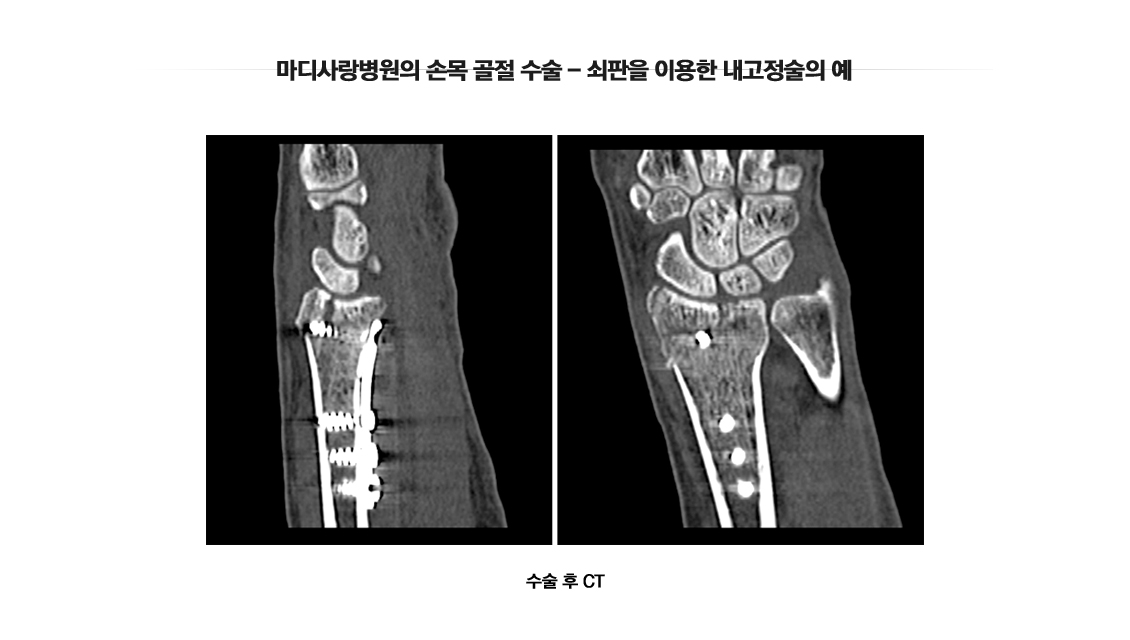

손목 골절수술

Wrist Fracture